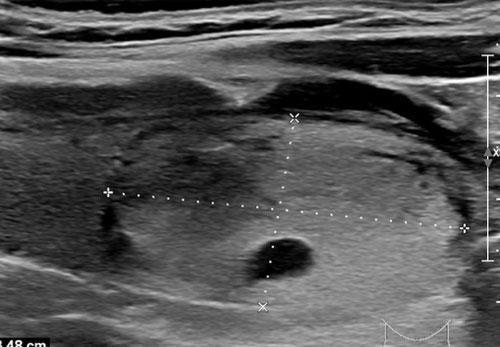

Trường hợp 2

Quan sát hình ảnh và xác định điểm TI-RADS.

Cuộn hình ảnh để xem điểm TI-RADS.